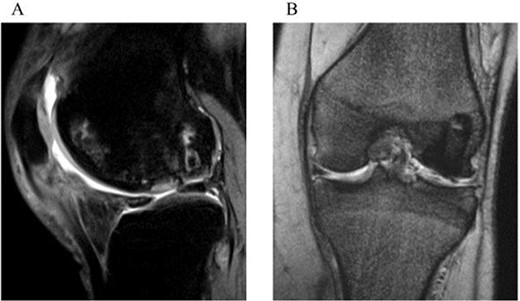

Preoperative radiographs and MRI. (a) An anteroposterior radiograph of the left knee shows the flattened lateral femoral condyle and irregular lateral joint surface. (b) A sagittal fat saturation T2-weighted image and (c) a coronal T2-weighted image show large osteonecrosis of the left lateral femoral condyle and lateral discoid meniscal tear associated with cyst formation. (d) A sagittal fat saturation T2-weighted image of right knee (contralateral knee) shows osteonecrosis of the lateral condyle similar to the left knee.

One year after surgery, the visual analog scale (VAS) score had improved to 0, and the ROM for extension and flexion were recovered to 0° and 140°, respectively. At 2 years, the Knee Injury and Osteoarthritis Outcome Score improved to 494, the VAS score remained at 0, and ROM of extension and flexion were fully recovered to 0°–145°. The follow-up MRI exhibited healing and consolidation of the osteochondral graft with the smooth articular surface attained at the grafted area (Fig. 4a and b).

Two-year postoperative MRI. A sagittal fat saturation T2-weighted image (a) and a coronal T2-weighted image (b) show smooth articular surface in the grafted area and consolidation of the transplanted bone plugs.